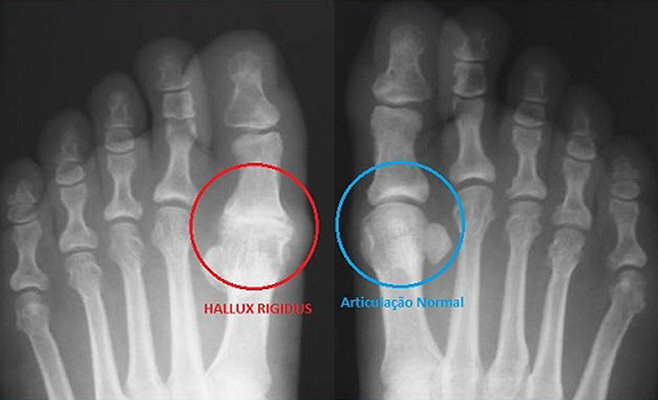

O diagnóstico é feito através da história clínica do paciente e do exame físico dos pés por um especialista. O raio X deve ser feito de ambos os pés e serve para avaliar o grau do Hallux Rígidus e o comprometimento articular, além de outras alterações concomitantes.

No Hallux Rigidus não ocorre o desvio lateral do dedo. A degeneração articular forma bicos ósseos, principalmente no dorso da articulação, quebloqueia o movimento e causa dor quando o dedo é submetido à extensão e flexão.

Hallux Rigidus é uma desordem degenerativa da maior articulação do primeiro dedo do pé (dedão). Essa alteração leva ao desgaste da cartilagem (artrose), com formação de bicos, protuberâncias ósseas e rigidez que pode progredir até o bloqueio completo do movimento do dedo. A dor pode variar de acordo com o grau de evolução da doença, com o tipo de calçado utilizado e com a atividade física exercida. Em 80 % dos casos existe o acometimento bilateral.